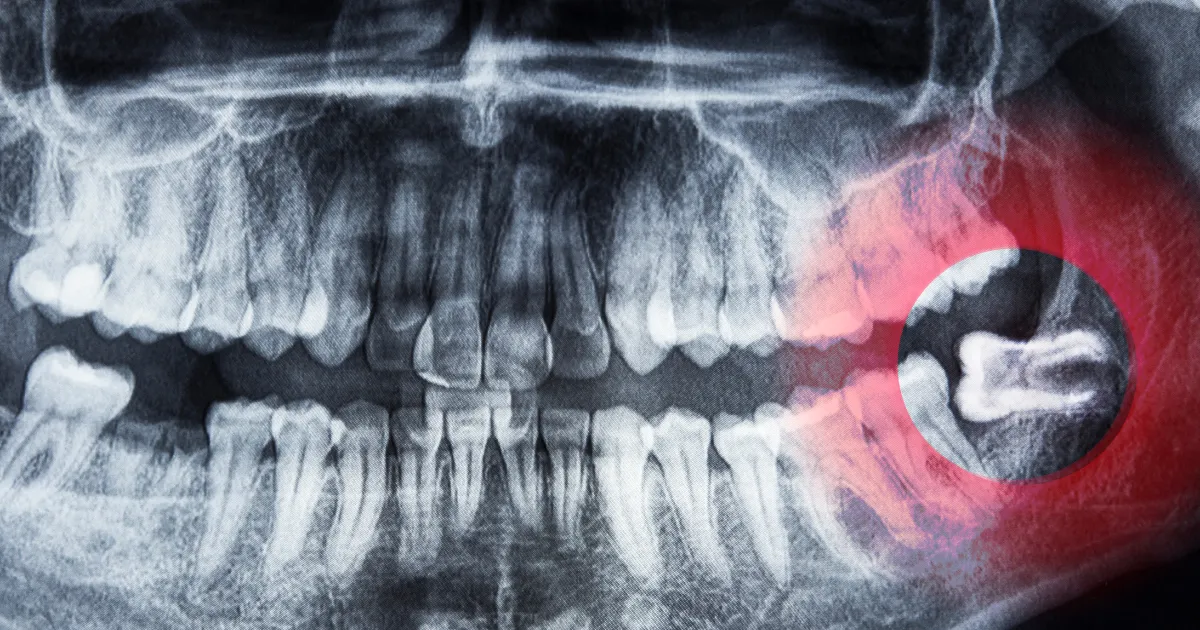

在下颌部拔除智齿时,如果牙齿位置接近神经,可能会引发麻痹。齿科哈米尔高田88使用CT扫描精确定位神经,尽量减少这种风险。